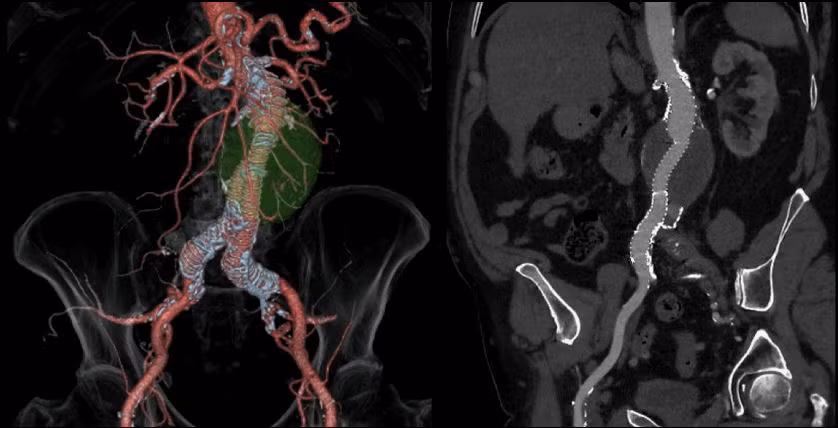

Bên cạnh đó còn có hệ thống chụp cắt lớp 128 dãy REVOLUTION EVO EVO GEN 2 hay còn gọi là CT-Scanner 128 dãy là một trong những thiết bị chẩn đoán hình ảnh hiện đại nhất, cải tiến hơn nhiều so với máy CT 64 dãy đang được sử dụng phổ biến hiện nay.

Khả năng cho hình ảnh đa chiều, sắc nét với độ phân giải đạt 0.24mm cho phép phát hiện những thương tổn có kích thước siêu nhỏ chỉ vài mm, CT-scanner 128 dãy của GE được sử dụng trong chụp và phân tích hình ảnh tim, phổi, đại tràng hay cơ quan có kích thước siêu nhỏ như mạch máu, đường dẫn khí và thậm chí là theo dõi ung thư tiến triển.

Đặc biệt, với chức năng điều chỉnh liều xạ phù hợp với từng đối tượng, thiết bị còn tích hợp chương trình chụp nhi an toàn hơn cho trẻ nhỏ.

|

| Hình ảnh mô phỏng mạch máu từ thiết bị CT-scanner 128 |